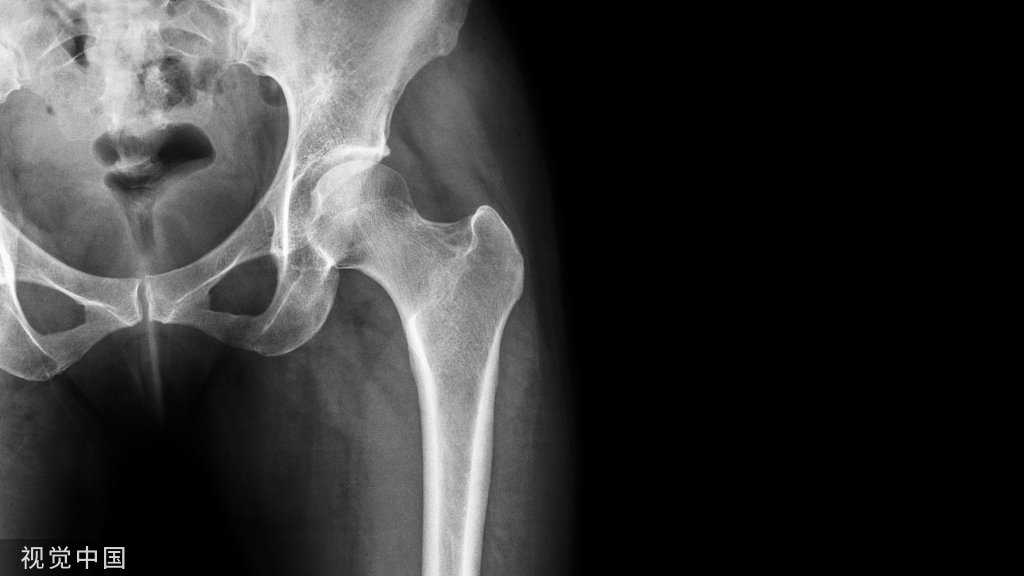

随访期间无陶瓷碎裂,5(5/85,5.9%)髋出现异响(吱吱声),3髋出现假体周围骨溶解(2髋位于股骨柄周围,Gruen分区 1和 7区,图1;1髋位于髋臼周围,DeLee -Charnley分区 2区,图2)。1例因Vancouver B2型股骨假体周围骨折而翻修(图3);1例合并系统性红斑狼疮的患者因假体周围关节感染而接受了清创术。任何原因导致再次手术的存活率为92.4%(95%置信区间为82.4%至100%)。